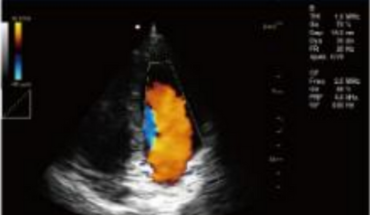

- B+CF (Dual Images)

- B+CF/DPDI+PW (Triplex)

- Phased Array Probe